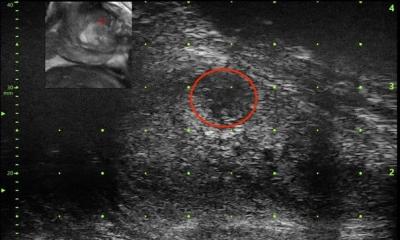

Die Fusion von Ultraschall- und MRT-Bildern für die Biopsie von auffälligen Arealen in der Prostata ist eine Möglichkeit, unnötige Biopsien zu vermeiden. Am Universitätsklinikum Bonn verfolgen Prof. Dr. Winfried Willinek und sein Team jedoch einen anderen Ansatz: Zunächst wird eine diagnostische Hochfeld-MRT an einem komplett digitalen MR-System durchgeführt.

Diese Bilder dienen dann bei auffälligen Befunden als Grundlage (Back-up) für eine stereotaktische, dreidimensionale, MR-gestützte Biopsie. Durch die MR-Kontrolle während der Biopsie kann die Gewebeverformung in der Prostata – im Gegensatz zur Bildfusion – unter Echtzeitbedingungen ermittelt werden. Die Diffusionsbildgebung ermöglicht während der Biopsie die Identifikation potenziell klinisch relevanter Tumoren, da die Veränderung des Gewebes in der Diffusionswichtung mit dem Gleason-Score korreliert. Dieses Vorgehen erlaubt eine äußerst sparsame Gewebsentnahme – oft reicht eine einzige Probenentnahme aus – was das Infektionsrisiko bei transrektalen Biopsien reduziert.